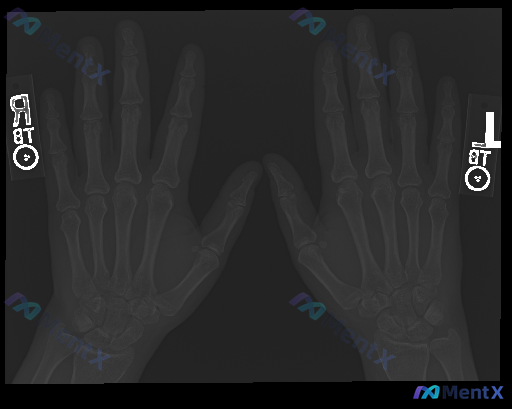

整理到一份双侧手部正位X光片的分析资料,情况有点值得讨论: 影像评估的客观描述是: - 各掌骨、指骨及腕骨骨皮质连续,未见明确骨折线、骨质破坏或异常硬化; - 骨小梁走行自然,骨密度尚均匀,未见弥漫性疏松; - 各关节(CMC、MCP、PIP、DIP)间隙清晰,宽度对称,对位良好,无脱位/半脱位;...